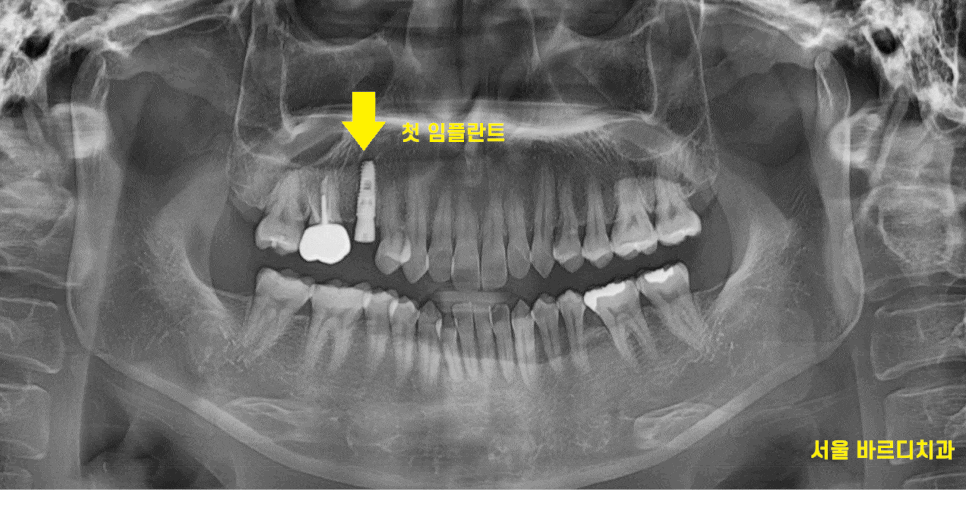

23.11.30

뿌리만 남은 치아입니다.

이정도로 부러졌으면 뽑고 임플란트를 해야하는데요.

24.04.30

환자분이 강동구 임플란트 수술을 결심하고

X-RAY를 촬영

그제서야 아...

왜 그동안 치과를 몇군데씩 다니셨나

이해가 되더라고요.

깨끗했습니다.

24.05.20

강동구 임플란트 1개 식립 완료한 사진입니다.